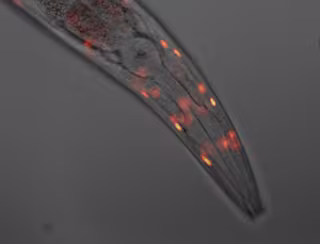

Imagen De Un C.Elegans

En declaraciones a Europa Press, el responsable de este aspecto del estudio, Adolfo Sánchez-Blanco, ha explicado que el C. elegans es "una especie de gusano" de un milímetro de largo perteneciente al filo nematoda que, por sus características, resulta "muy útil" como "cobaya" de laboratorio, ya que posee "cerca de un 70 por ciento de genes similares a los del hombre".

Además, su color transparente permite examinar su desarrollo en el microscopio y tiene "un coste muy bajo" de mantenimiento, ya que se encuentra comúnmente en el humus del suelo en lugares con un rango de temperatura en algún momento del año entre los 15 y los 25 grados y se puede cultivar en una placa petri, al igual que las bacterias Escherichia coli de las que se alimenta.